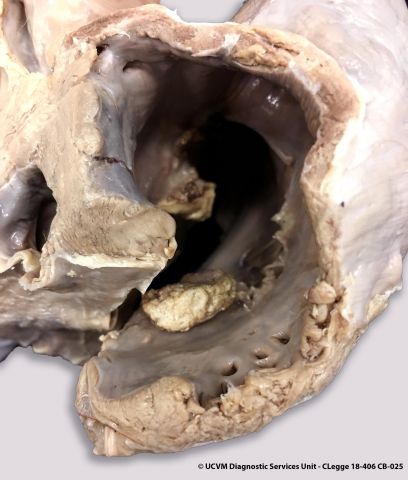

Species: Equid, Horse

Heart, AV valve

Vegetative valvular endocarditis

Irregular yellow-red or yellow-gray vegetations on the valve leaflets, with underlying ulcerations